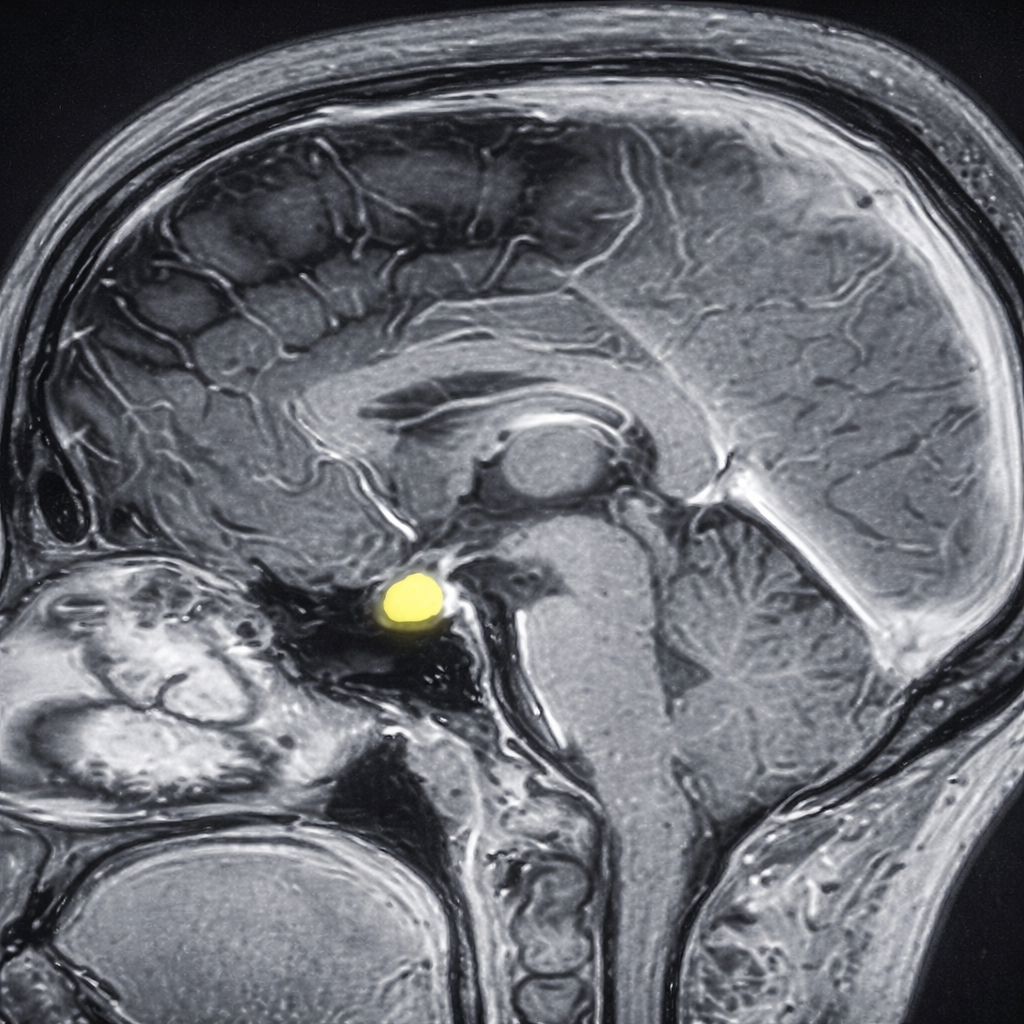

Quistes en la bolsa de Rathke

- Resonancia magnética (MRI), la cual permite visualizar el quiste y su relación con estructuras cercanas.